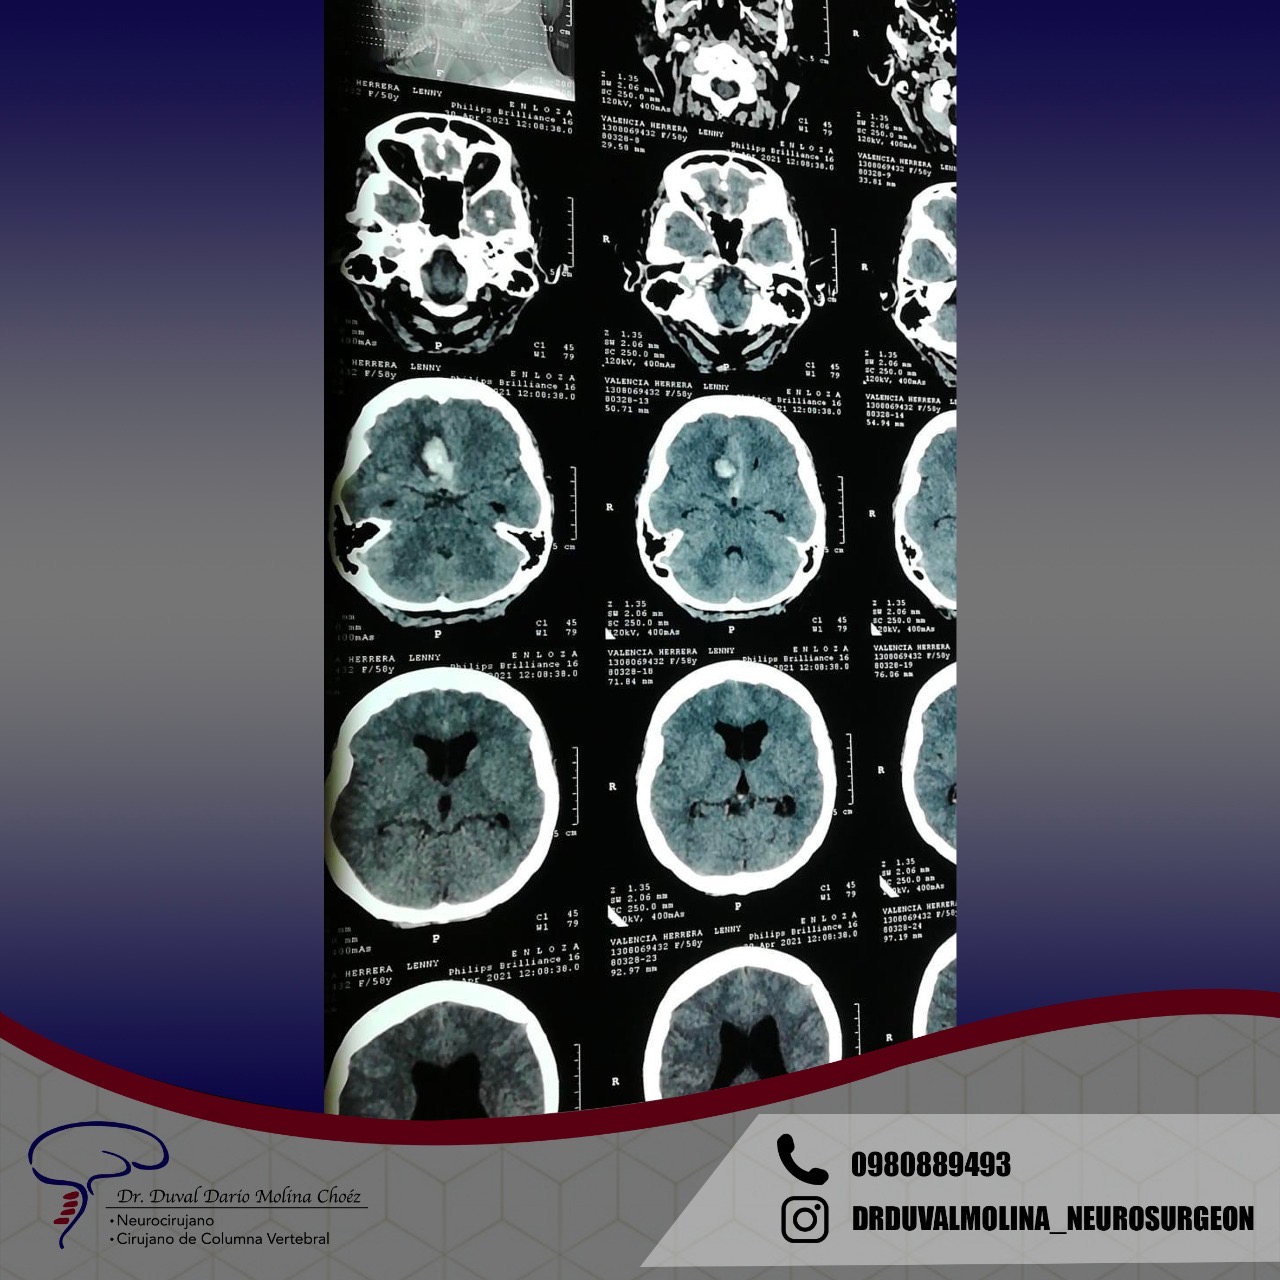

Aneurysms are bulges in an arterial wall that represent weak points. They are found in about 2-3% of the population and usually remain undetected until they rupture. A ruptured aneurysm leads to a very severe headache and a rapid onset of neurological problems. The characteristic pattern of hemorrhage is called a “subarachnoid hemorrhage.”

Aneurysms can also cause instant death or result in permanent disability. In some cases, there is a strong family history or genetic condition. The most common inherited disorder is adult polycystic kidney disease. Trigger factors for aneurysm rupture include smoking, poorly controlled hypertension, and overexertion. If left untreated, there is a cumulative annual risk of rupture and periodic screening is recommended.

The typical bleeding pattern is seen after aneurysm rupture. The shape and location of the aneurysm can predict its behavior and also determine which treatment is preferred. Alternatively, if the aneurysm has a low risk of rupture or a high surgical risk, we may choose to surveil it with serial imaging. The intervention is designed to block the blood flow into the aneurysm, therefore eliminating the risk of hemorrhage. It can be performed endovascularly – by filling the aneurysm from within (“endovascular coiling”), or by open microsurgical techniques (“clipping”).